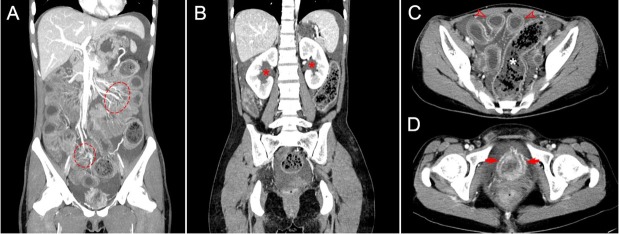

内部风暴:狼疮的腹部和泌尿系统并发症。

The storm inside: Abdominal and urinary complications in lupus.